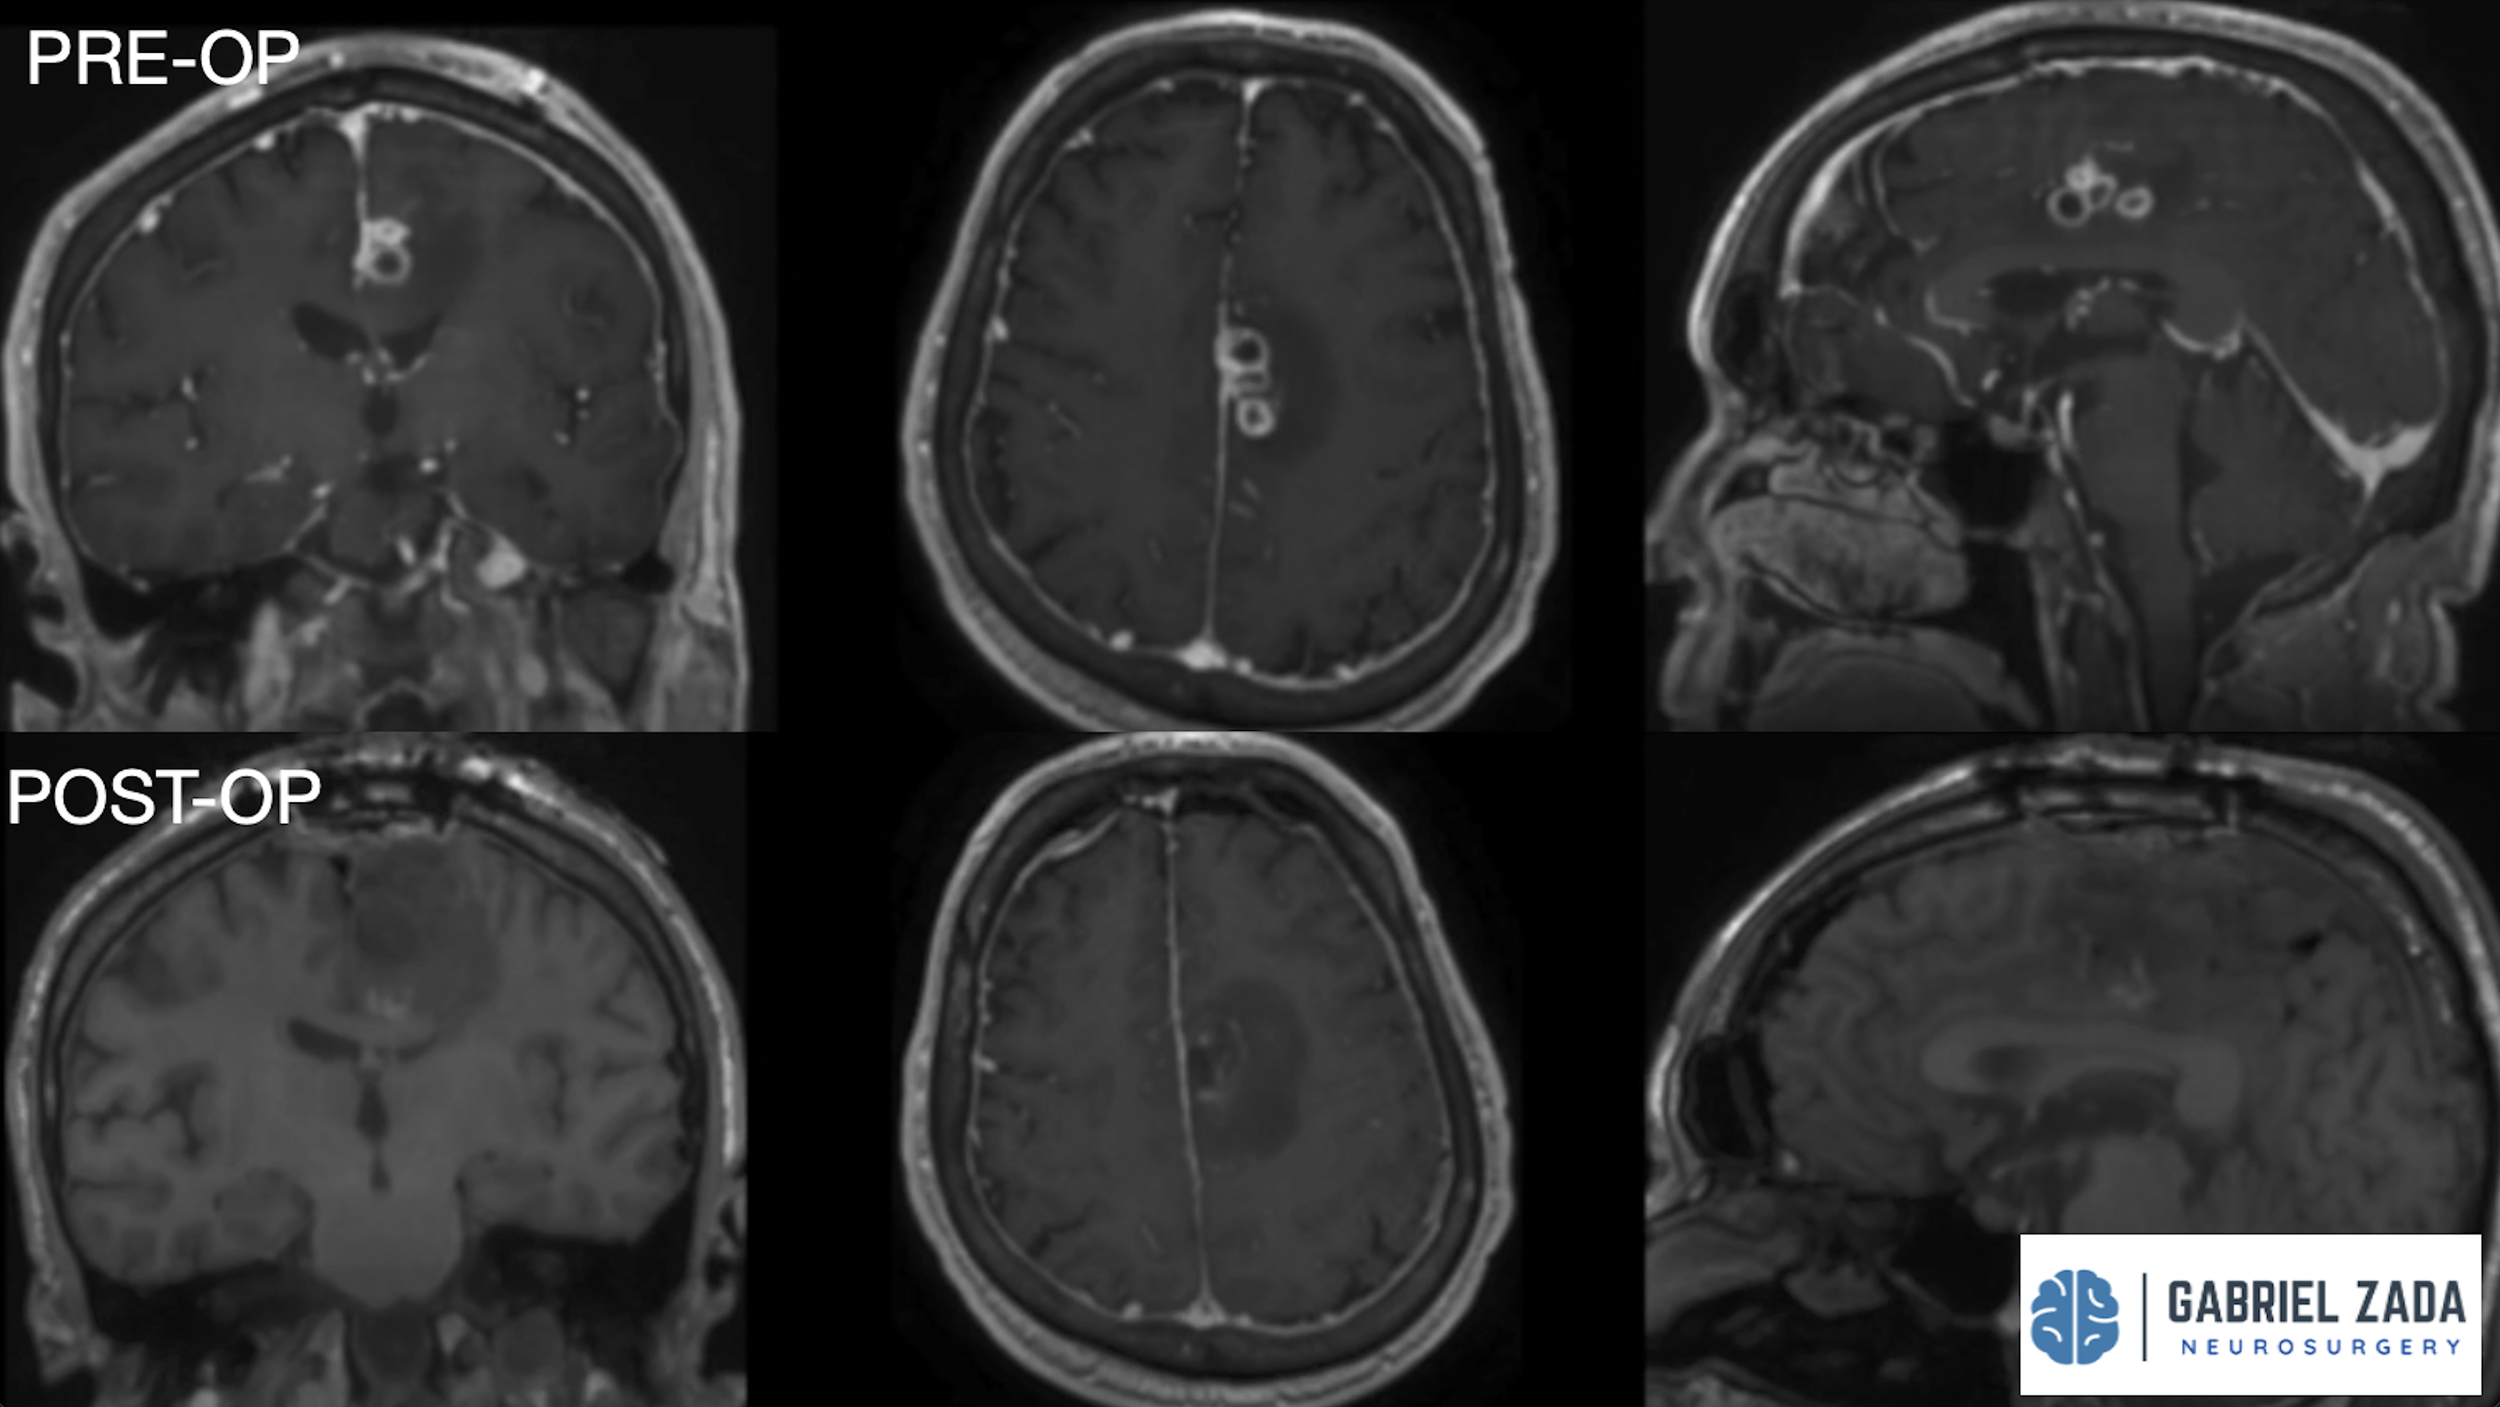

Explore this comprehensive gallery featuring pre‑ and post‑operative imaging of patients with skull‑base tumors treated by Gabriel Zada, MD, MS, FAANS, FACS. These cases highlight Dr. Zada’s expertise in advanced neurosurgical techniques and outcomes.

*Representative cases shown for educational purposes. All images de-identified. Individual results vary.